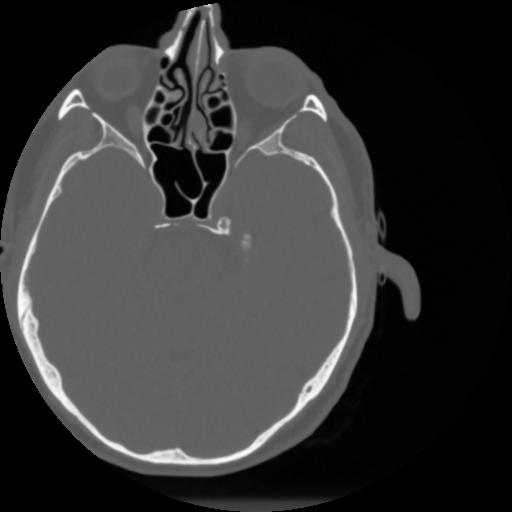

4 CEREBRO,,Vol,0.5,CEREBRO,,